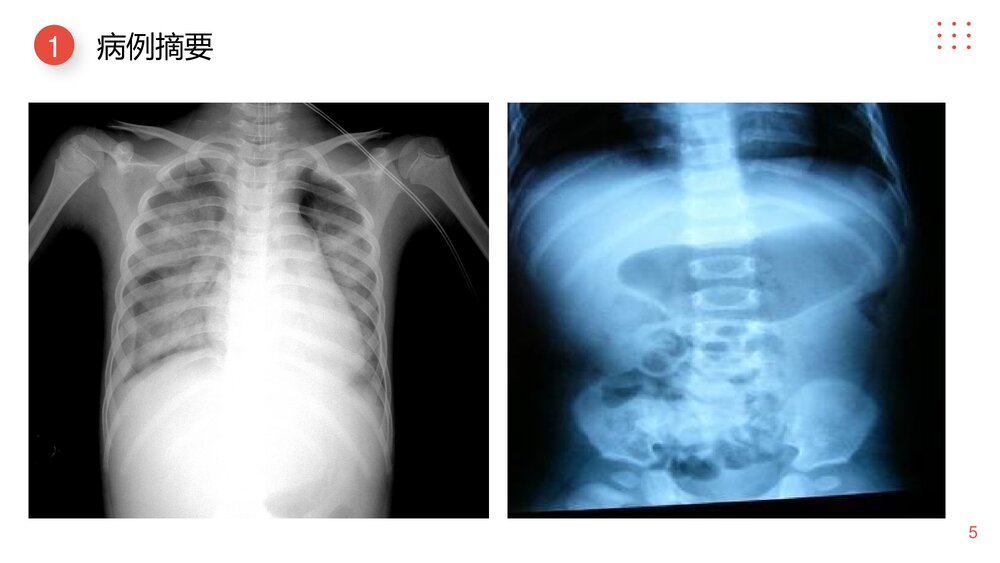

20XXLogo小儿肠套叠护理查房汇报人:XXX目录contentsLogo病例摘要1护理评估2护理诊断3预期目标4护理措施5护理评价6PART01病例摘要Whentheycleartheirminds,theyfeelsosorrytobringhurttotheonestheylove.41简要病史姓名:王XX(28床)性别:男年龄:3个月住院时间:20XX年10月21日主因:阵发性哭闹伴呕吐1天,血便4次PE:神志清楚,精神欠佳,哭时无泪,面色稍苍白,未闻及干湿性音,心音有力,律齐,心率120次/分,腹软有压痛,左下腹科触及包块,质硬,有触痛,活动度可。神经系统查体未见异常。51病例摘要61现病史当日夜间患儿出现呕吐,为非喷射状,呕吐物为胃内容物,遂请我科值班医生会诊,初步诊断为肠套叠,建议转科治疗。患儿于5AM转至我科。A行空气灌肠复位失败,下病重,给于特级护理,禁食水,胃肠减...